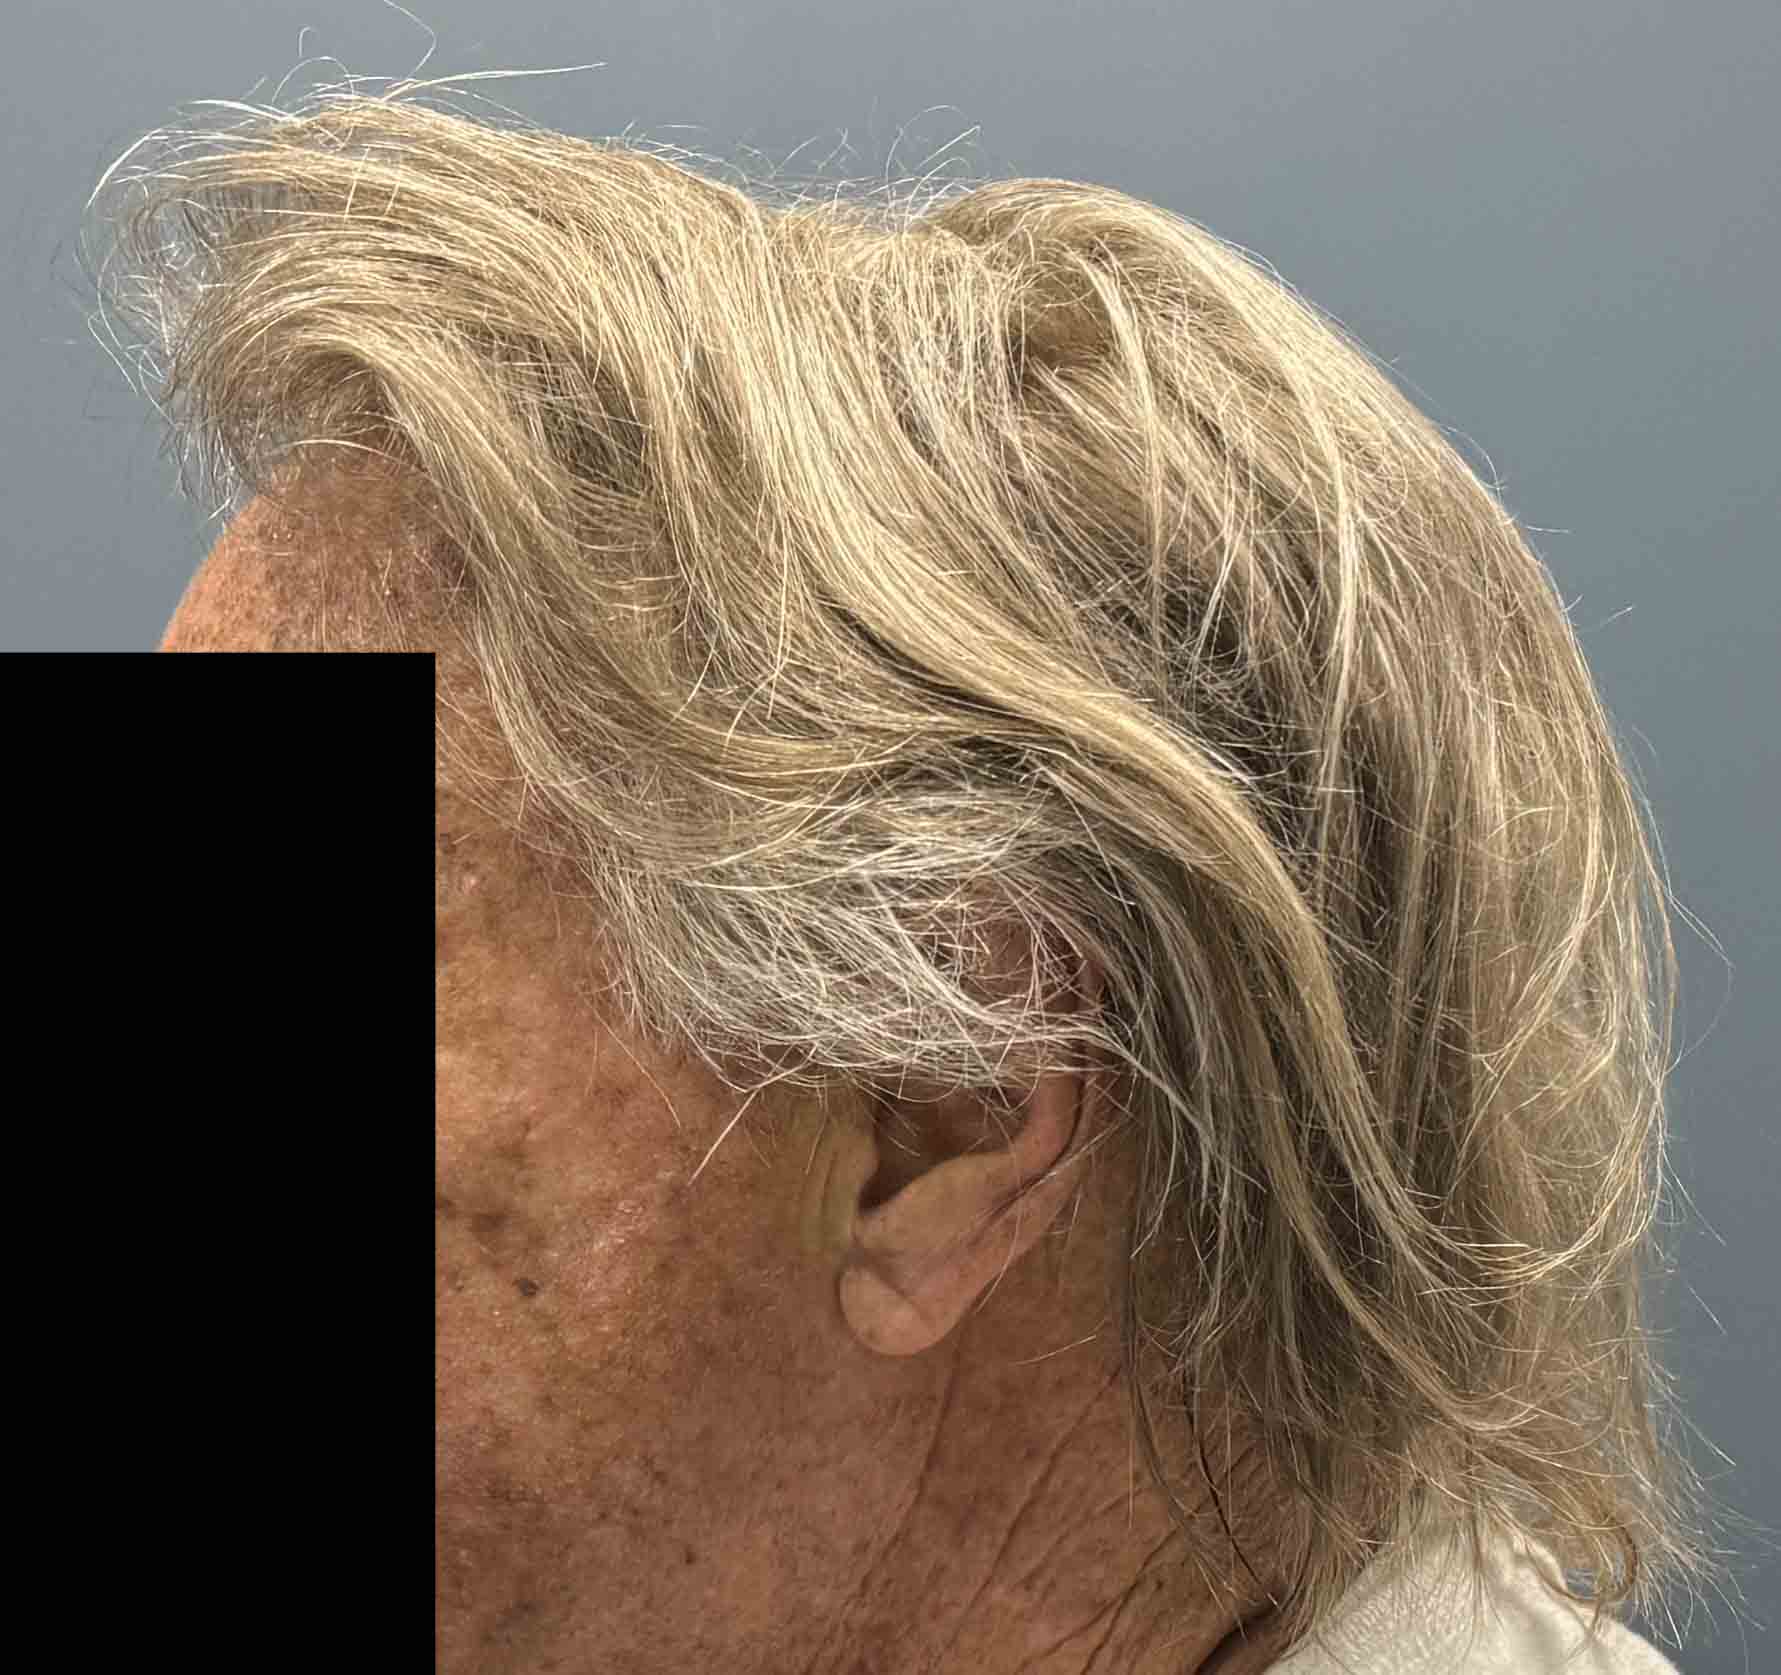

Patient 175

Older female (70) with lifelong desire to improve the projection of the crown of her skull.

Placement of 80cc custom skull implant for crown of head augmentation.

Older female (70) with lifelong desire to improve the projection of the crown of her skull.

Placement of 80cc custom skull implant for crown of head augmentation.